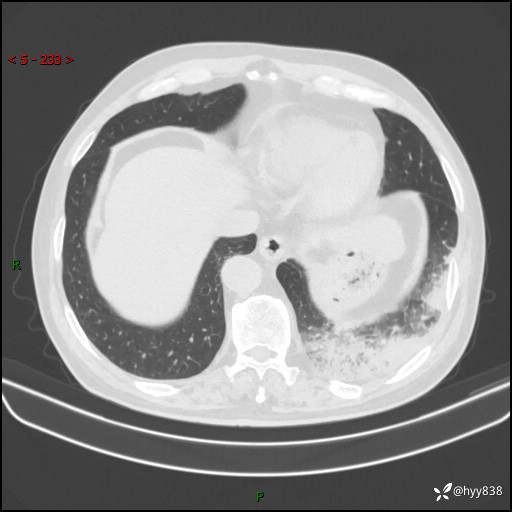

【患者信息】:59岁/男

【主诉】:发热伴咳嗽3天

【现病史及既往史】:患者3天前无明显诱因出现发热,体温最高达38.6℃,伴有咳嗽,干咳为主,感乏力、肌肉酸痛,无明显头晕头痛、鼻塞、流涕、呼吸困难、胸痛、恶心呕吐、腹痛腹泻、尿频尿急等不适,于当地诊所输液治疗3天感症状无好转,仍有间断发热、咳嗽,现为求进一步诊治,于我院门诊就诊,门诊以“发热待查”收入我科进一步诊治。 患者自发病以来,精神、饮食、睡眠欠佳,大小便正常,体力、体重无明显变化。

【检查】:胸部CT平扫